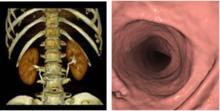

早期醫學圖像的配準目的,是為了把顯示人體不同信息(結構信息和功能信息)的醫學圖像放到統一坐標系中顯示。隨著腦部結構形態學分析研究的進步,出現了同病人不同時期及同種疾病的病人群體圖像數據配準,以及標準圖譜到特定圖像數據集配準研究。為了消除成像過程中對象運動的影響,圖像配準也是時序圖像分析的第一步。尋找物體在不同影像中對應像素點的關係是醫學圖像配準的基本任務。通過尋找適當的空間變換,使圖像數據達到空間位置上的定位和配準,進而進行圖像融合。圖像配準方法可以分為基於外部特徵和基於內部特徵兩類。使用外部特徵的通過人工設定的標記點實現配準,如立體框架定位、皮膚標記法等;而基於內部特徵方法通過尋找圖像內部解剖結構上的特徵點或外部輪廓和表面的對應關係實現配準。互信息量是隨機變數統計相關性的測度,在醫學圖像配準中得到廣泛套用 。由於最大互信息方法不需要假設不同成像模式下的圖像灰度的相關性,也無需對圖像進行分割和預處理,非常適合三維多模醫學圖像配準,具有精度高、魯棒性強的特點。目前,醫學圖像配準技術和分割技術一樣,出現了很多成熟的方法和軟體,是醫學圖像分析中的基本技術之一。

醫學圖像分析圖2. 醫學圖像配準融合